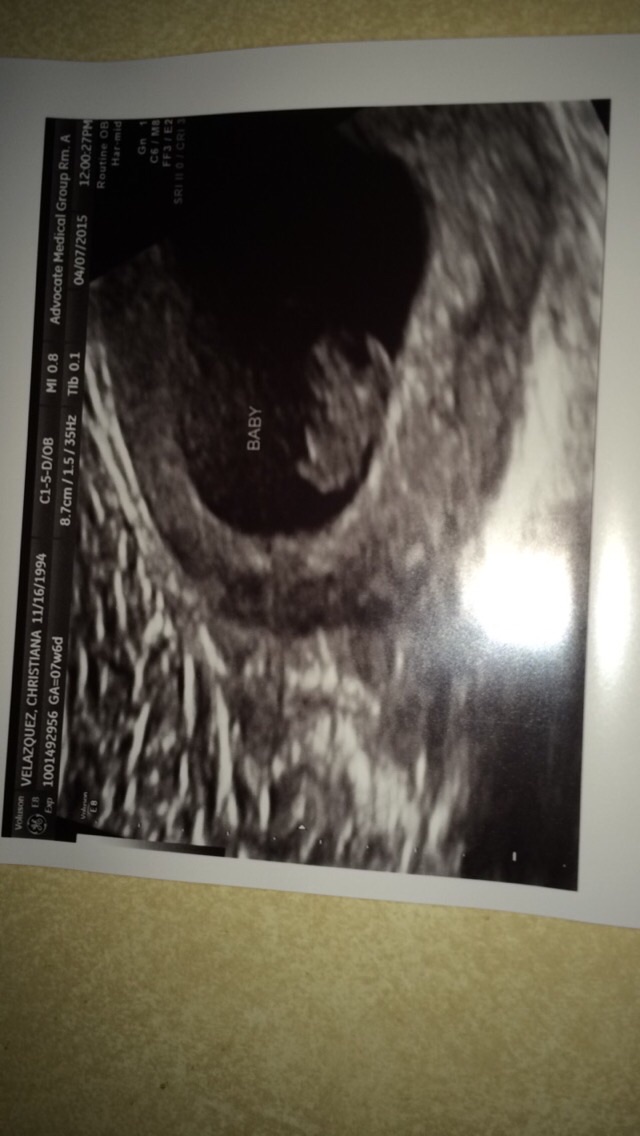

This was taken at exactly 8 weeks! Which was April 7th. I was so happy to see a little baby because when my pregnancy first started we thought I was farther along than I was so when I got an ultrasound it was just a sac which was very scary at the time.